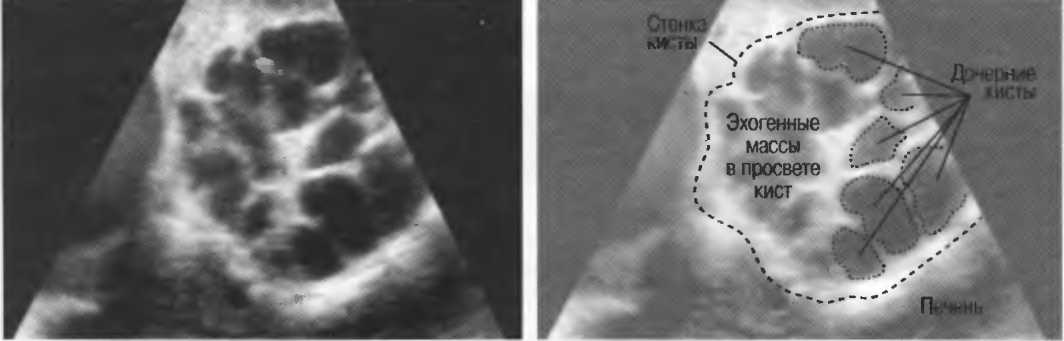

Кисты

Киста, как правило, визуализируется в виде анэхогенной зоны, при этом структуры, расположенные за кистой, обычно усилены: полость кисты анэхогенна, поскольку в ней нет структур с различным акустическим сопротивлением. В результате того что жидкость не поглощает ультразвук в такой же степени, что и ткань, эхо-сигналы от расположенных позади кисты структур гиперкомпенсированы сканером и выглядят усиленными — появляется эффект усиления задней стенки (рис. 14а,б).

Киста определяется в виде анэхогенной зоны с усилением по задней стенке. Если в кисте есть внутренние зхоструктуры, то они могут быть реальными или являться артефактами.

Артефакты могут определяться в любой кистозной структуре (такой, например, как мочевой пузырь или желчный пузырь) и чаще определяются ближе кпереди, становясь менее выраженными на глубине. Они исчезают или меняют свой характер при изменении положения датчика. Но истинные структуры в кисте, такие как перегородки, сохраняют свое местоположение независимо от положения датчика. Истинные отражения имеют место при наличии сгустка крови, гноя, некротической взвеси, и все это чаще визуализируется по задней стенке: если эти структуры не фиксированы к стенке, они изменяют свое положение при перемене положения тела пациента (рис. 16).

Рис. 16а. Злокачественная киста яичника: крупная киста с внутренней перегородкой, которая остается в прежнем положении при сканировании пациентки в различных положениях.